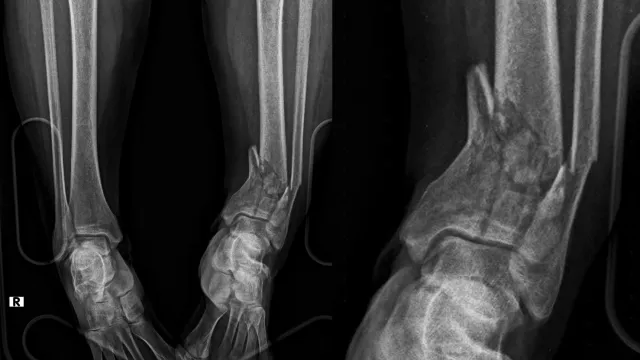

Travma ve Kırık Cerrahisi

Travma ve kırık cerrahisinde doğru planlama ve deneyim tedavinin başarısı için çok önemlidir. Cerrahisiz veya alternatif yöntemlerle tedavi mümkün olduğu düşüncesi, hastaları son yıllarda yanlış kararlara yönlendirmektedir. Her kırık kaynasa da doğru açıda kaynaması, ekleminizi sağlıklı kullanabilmeniz için hayati önem taşır.

Travma Sonrası Kırık Cerrahisi

Travmalar, günlük yaşamda en sık karşılaşılan acil durumlardan biridir. Trafik kazaları, yüksekten düşmeler, spor yaralanmaları veya iş kazaları sonucu oluşan kırıklar, hızlı ve doğru müdahale edilmediğinde kalıcı sakatlıklara yol açabilir....